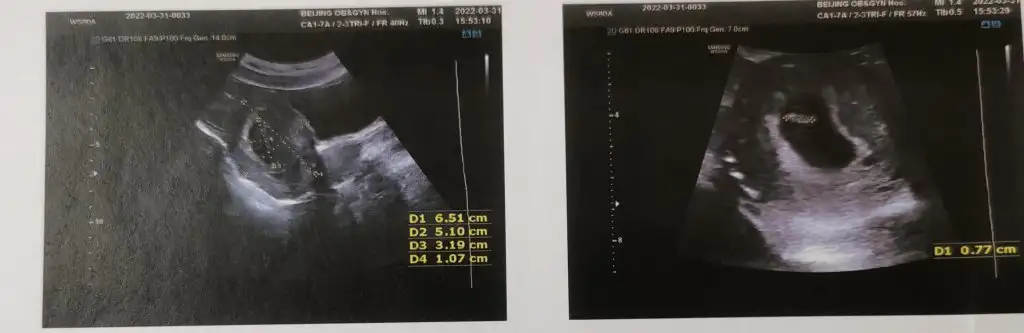

Bana da yorum yapabilir misiniz?

1.Resim 6+3

2.Resim 11+5

3.Resim 13+4